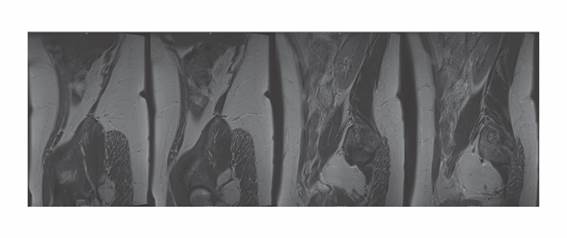

En julio de 2022 se realizó la RM que reportó abombamiento discal posterior L5-S1, ya conocido (Figura 1). En una nueva consulta de Ginecología se decidió la retirada del DIU, indiciando ejercicios de suelo pélvico. Dada la persistencia de las sintomatologías sin mejoría tras los ejercicios indicados se solicitó nueva RM pelviana.

Figura 1. RM lumbar con discreto abombamiento L5-S1.